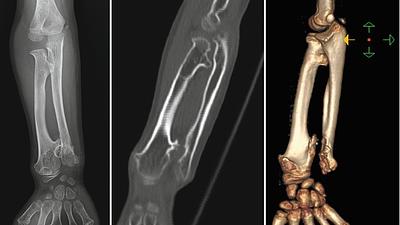

radiology.jpeg

Radiologia é fundamental no diagnóstico precoce de tumores ósseos pediátricos

O osteossarcoma é responsável por aproximadamente 60% dos tumores ósseos malignos em crianças e adolescentes, com a maior incidência entre 10 e 20 anos de idade.